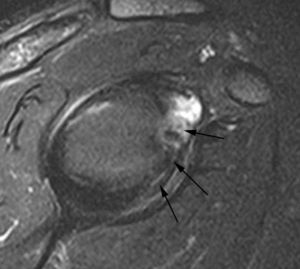

GLAD (gleno labral articular disruption)

El GLAD puede acompañar a cualquiera de las patologías que se discuten en este artículo, afectando al LG. Se trata de una disrupción de un fragmento de cartílago articular junto a la lesión del LG20 (fig. 16).

Fig. 16.--Lesión de GLAD (gleno labral articular disruption). Artrorresonancia axial T1 con supresión grasa donde se puede observar una rotura del labio glenoideo anterior y posterior (flecha). El labio glenoideo anterior está más desplazado. Se ve un fragmento de cartílago articular separado de su posición normal en la cavidad glenoidea y adherido al labio glenoideo anterior (cabezas de flecha).